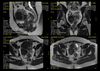

Qu’est-ce qu’une IRM abdomino-pelvienne ?

L’IRM abdomino-pelvienne est un examen qui consiste à visualiser les organes de la région abdominale (foie, voies biliaires, pancréas, rate, reins…) et de la région pelvienne (vessie, urètre, utérus, ovaires, prostate, rectum…)

Déroulement de l’IRM abdomino-pelvienne

La durée d’examen est d’environ 15 minutes.

Vous serez installé dans l’appareil, allongé sur le dos avec une antenne spécifique positionnée sur la région abdomino-pelvienne.